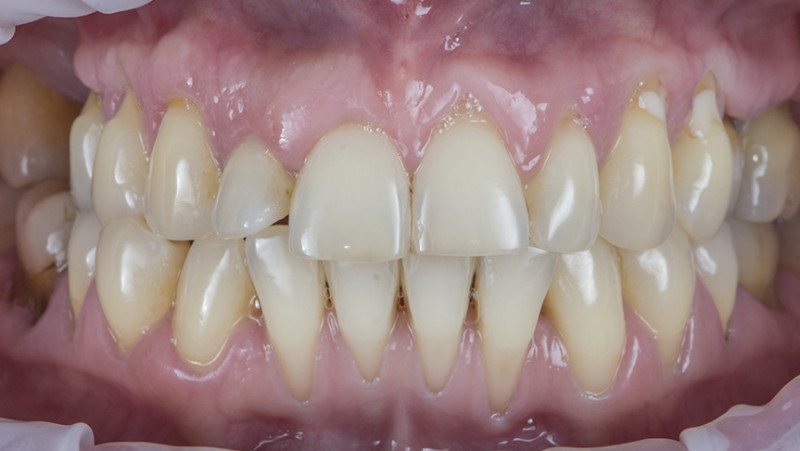

Установка коронки на зуб

Провели швейцарскую профгигиену. Перелечили зубы с несостоятельными пломбами и воспалениями. Удалили 7 зубов на верхней и нижней челюсти с одномоментной имплантацией 9 имплантатами, костной пластикой и пластикой десны. После приживления имплантатов установили временные коронки. Изготовили и установили абатменты Procera и 28 единиц керамических коронок EMAX.